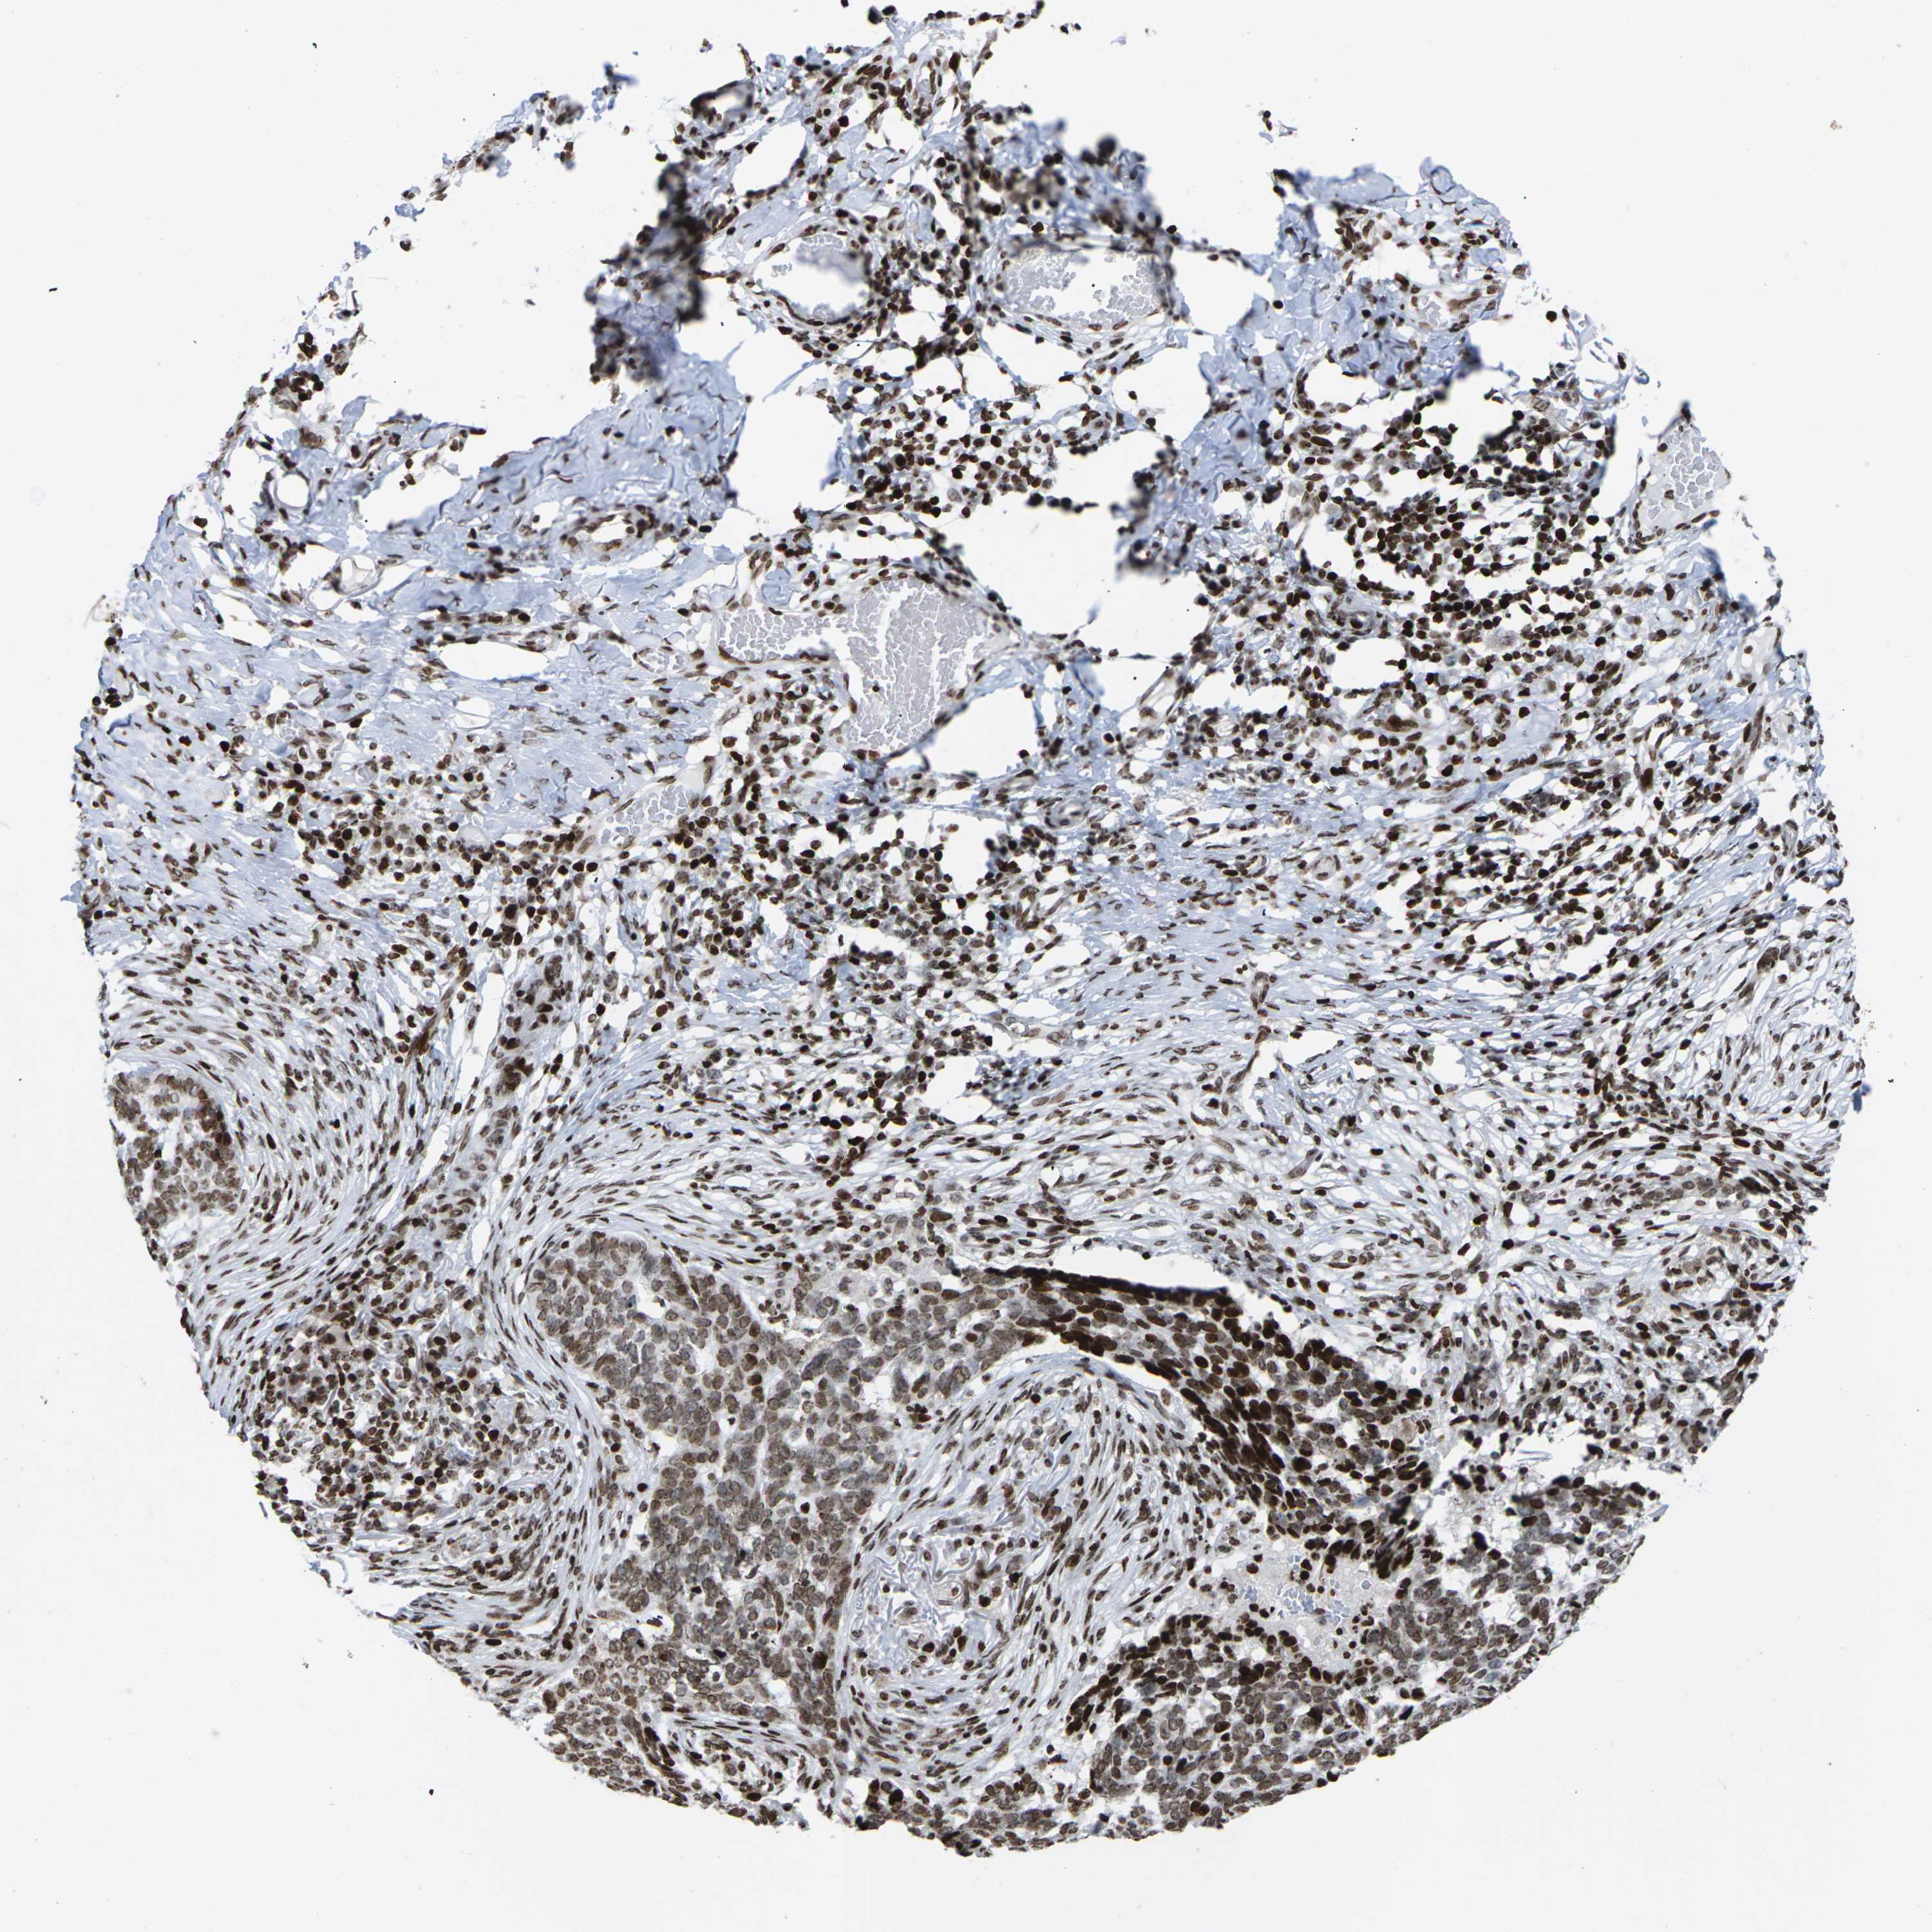

SKIN CANCER - Protein expressioni

A mouse-over function shows sample information and annotation data. Click on an image to view it in a full screen mode. Samples can be filtered based on level of antibody staining by selecting one or several of the following categories: high, medium, low and not detected. The assay and annotation is described here.

Each image is clickable and will lead to virtual microscopy that enables deeper exploration of all samples and also displays staining intensity scores, fraction scores and subcellular localization as well as patient and tissue information for each sample.

Antibody CAB011506

Squamous cell carcinoma, NOS